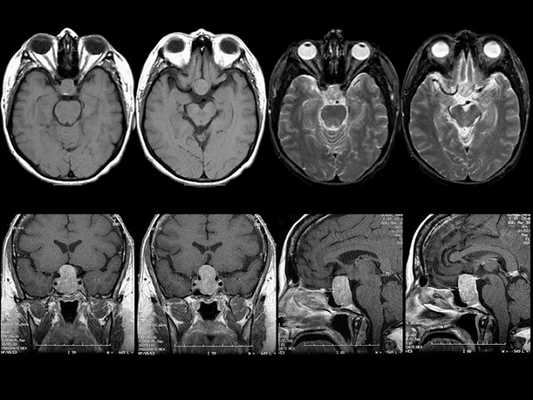

Гигантская аденома гипофиза на МРТ

МРТ гипофиза при краниофарингиоме: сканы в разных проекциях

Наиболее часто на томограммах обнаруживают аденому гипофиза - доброкачественное новообразование, исходящее из передней доли. Опухоли могут произрастать из любого отдела питуитарной железы, что вызывает многообразие клинических проявлений. Аденома гипофиза локализуется в области турецкого седла, при значительном росте возможно распространение на костные пазухи, желудочки головного мозга, базальную поверхность больших полушарий. Вышеописанные структуры врач может рассматривать в виде многоплоскостных объемных изображений, состоящих из множества срезов, что позволяет уточнить:

- размеры и границы опухоли;

- ее взаимосвязь с окружающими структурами - супраселлярной и мозговой цистернами, перекрестом зрительных нервов, пазухой основной кости, спинкой и бугорком седла, кавернозными синусами и пр.;

- предположительный характер (доброкачественный или злокачественный, первичный или метастатический, окончательная верификация доступна после морфологического исследования). Анализируют постконтрастные снимки, интенсивность накопления красителя (аденомы в подавляющем большинстве задерживают препарат медленнее, чем ткани гипофиза, для злокачественных опухолей характерен усиленный ангиогенез). Дифференциацию проводят с краниофарингиомой, кистой кармана Ратке и арахноидальной жидкостной полостью, имеющих схожие признаки на МР-сканах.

Специалист делает вывод о наличии новообразования гипофиза при обнаружении деформации дна одноименной ямки, асимметрии самой железы, неоднородности ее структуры, смещении воронки от срединной линии.